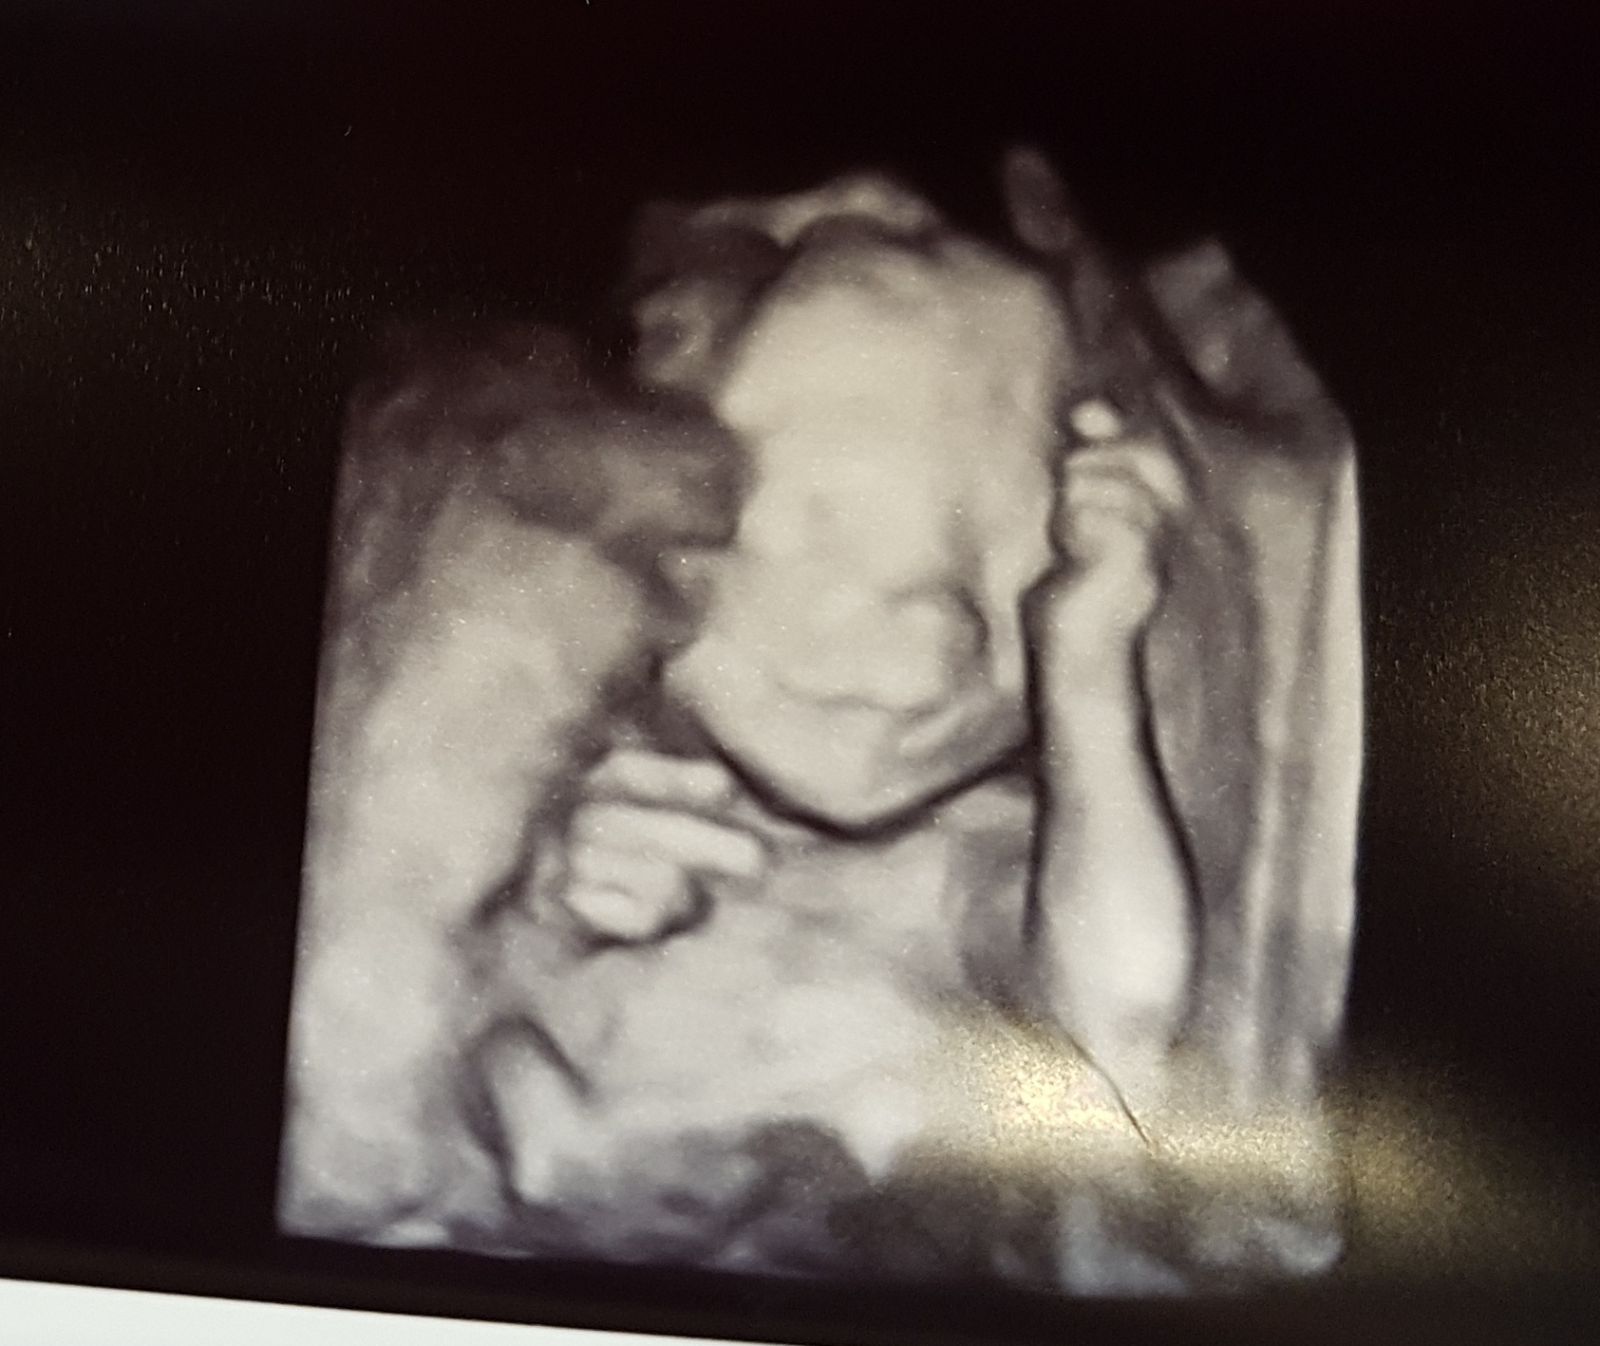

ja oczywiście nie uważam że ciąża in vitro jest jakas innaTu malo ktory lekarz uznaje ciaze Po ivf jako inna niz te zaplodniona naturalnie stad usg dopiero w 12 tc ( Ja 13 t 4d)

Pierwsze usg ribi kkinika widzi serduszko i tyle